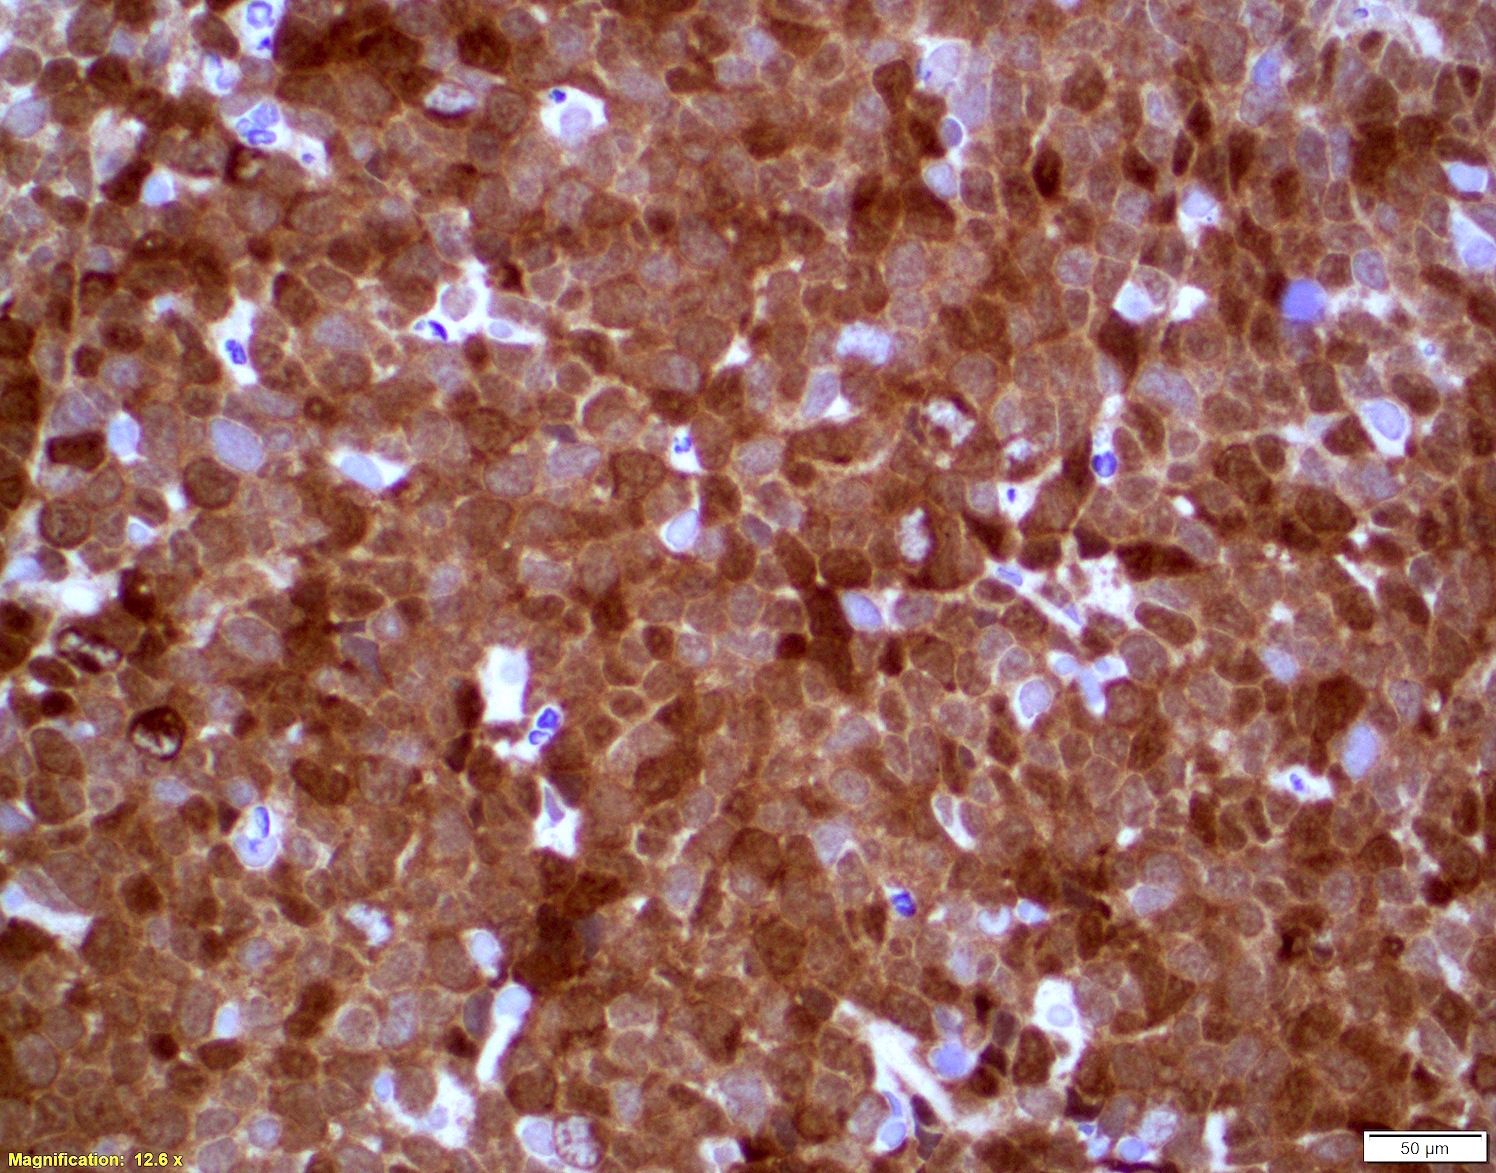

Microscopic (histologic) images

Positive stains

- Immunophenotype similar to classic mantle cell lymphoma

- Cyclin D1

- CD19, CD20, CD43, sIg, IgM with or without IgD

- CD5 (> 95%), SOX11 (> 90%)